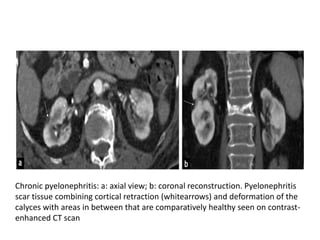

Chronic pyelonephritis: a: axial view; b: coronal reconstruction. Pyelonephritis

scar tissue combining cortical retraction (whitearrows) and deformation of the

calyces with areas in between that are comparatively healthy seen on contrast-

enhanced CT scan